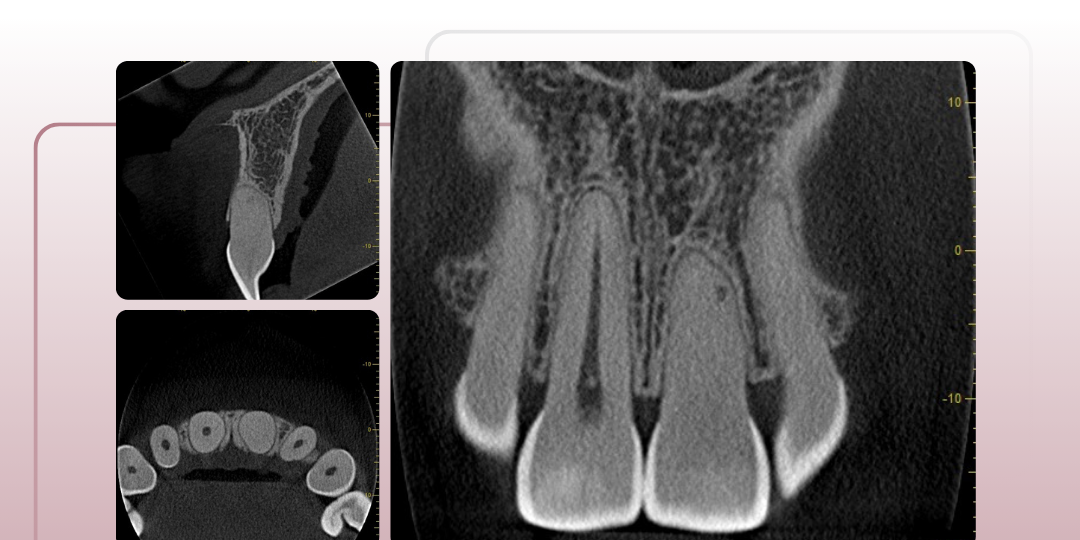

Quando um dente sofre um trauma, a vitalidade pulpar pode ser comprometida, mas nem sempre o teste de sensibilidade fornece uma resposta definitiva. Neste caso, o paciente apresentava um teste inconclusivo. Por isso, temos a tomografia como aliada em casos pós-trauma.

A tomografia computadorizada de feixe cônico (CBCT) revelou um conduto radicular calcificado, mas sem lesão periapical associada. Essa informação tornou-se determinante para a conduta clínica: não havia, naquele momento, indícios de necrose, e o caso encaminhou-se para acompanhamento tomográfico.

Por que a tomografia foi essencial nesse cenário?

✔ Confirmou a integridade dos tecidos periapicais, permitindo uma conduta mais conservadora.

✔ Estabeleceu um parâmetro para comparações futuras, auxiliando na decisão sobre necessidade ou não de intervenção.

A tomografia fornece dados objetivos para um diagnóstico mais seguro e uma abordagem baseada em evidências.